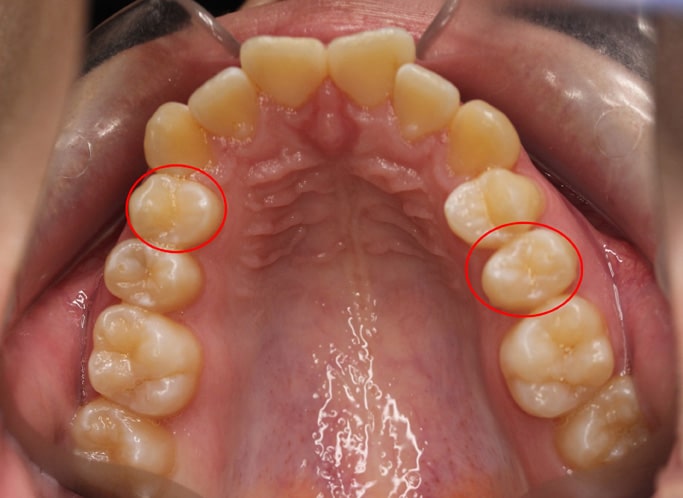

- Un manque de place marqué dans l’arcade supérieure.

- Une mâchoire supérieure comprimée.

- Une ligne médiane supérieure décalée sur la gauche, ne coïncidant pas avec celle du bas.

Après analyse, le schéma le plus pertinent pour obtenir un sourire équilibré et une mastication optimale passait par l’extraction de deux prémolaires dans l’arcade supérieure. La ligne médiane étant décalée à gauche, il a fallu ajuster : extraction de la première prémolaire à droite et de la deuxième prémolaire à gauche. Ce choix permettait à la fois de réaligner la ligne médiane et d’assurer une occlusion correcte.